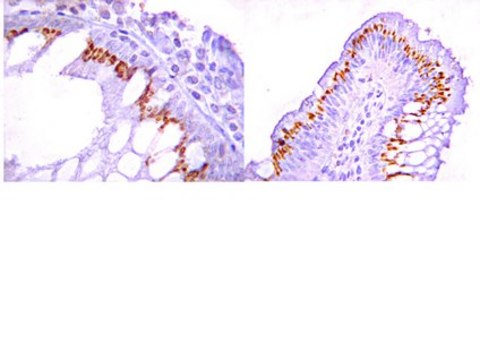

Evaluated by immunohistochemistry (paraffin) in human gastric mucosa.

Immunohistochemistry(paraffin): 1:50-1:200 dilution of this antibody detected ROR2 in human gastric mucosa.